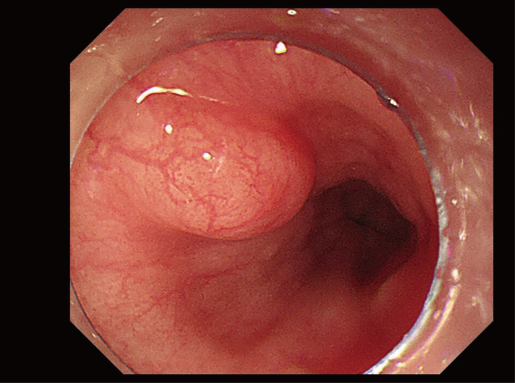

30836a0c45f36bfa78d0262156d5e61c.png

195bf9db8d1435c8e97db89b1c379104.png

图:食管上皮下病变-食管平滑肌瘤